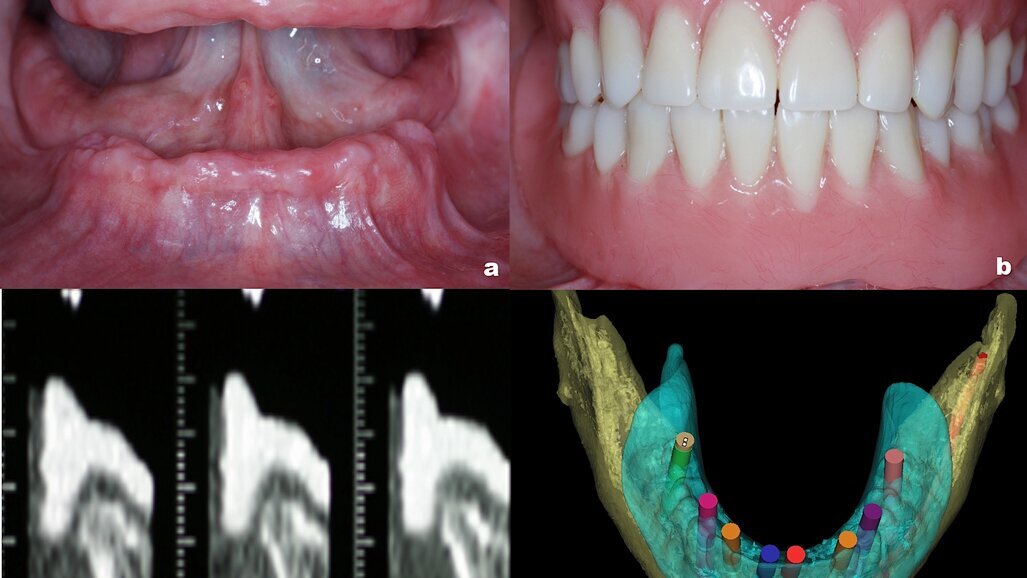

Figura 1a. Condición inicial del paciente totalmente edéntulo. Figura 1b. Prótesis transicional fabricada a partir del encerado diagnóstico utilizada como guía radiográfica. Figura 1c. Cortes realizados a intervalos de 1mm en la mandíbula. Figura 1d. Relación del hueso residual con respecto al diseño propuesto de la restauración final.

En el caso de la implantología oral, la tomografía se utiliza en combinación con la guía quirúrgica como referencia para practicar el estudio. Una vez fabricada la guía a partir del encerado diagnóstico, se hace una prueba clínica. La verificación clínica de la guía es el aspecto más importante en la identificación del problema, y en la expectativa que se tiene del resultado final de la rehabilitación. La guía debe cortarse cuidadosamente para reproducir fielmente las características, tanto horizontales como verticales, de la prótesis final. Otra opción es utilizar una prótesis transicional fabricada a partir del mismo encerado diagnóstico (Figuras 1a-1b); si el paciente y el clínico quedan satisfechos con el resultado proyectado, la guía es cubierta o reproducida con un medio de contraste y se practica el estudio tomográfico. Los cortes se realizan a intervalos de 1.5mm en la maxila y a intervalos de 1mm en la mandíbula. Así se obtienen imágenes computarizadas, tanto en el plano frontal como en el sagital8.

El análisis radiográfico muestra la silueta de los dientes del encerado diagnóstico en vistas axiales, sagitales y panorámicas. Son necesarios marcadores radioopacos como puntos de referencia. Cada marcador tiene que extenderse a lo largo del eje longitudinal del diente, desde la porción coronal hasta el área cervical de la corona. La función de la guía es establecer las características del tejido óseo y su relación directa con el tipo de restauración planeada por un parámetro que sólo este tipo de recurso puede determinar, como es el ángulo que guarda la cresta residual con respecto al perfil axial propuesto de la restauración final (Figuras 1c-1d). Con esto se puede calcular la cantidad de tejido óseo y la viabilidad del tipo de restauración planeada8.